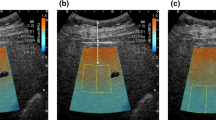

A four-point VGS based on comparisons of the brightness of the liver with those of hepatic vessels on unenhanced CT images was developed as follows: grade 0 (G0; hepatic vessels showing lower attenuation than the hepatic parenchyma, with no or minimal margin blurring in less than one-third of the liver), grade 1 (G1; hepatic vessels showing lower attenuation than hepatic parenchyma but with margin blurring in more than one-third of the liver), grade 2 (G2; hepatic vessels showing the same attenuation as hepatic parenchyma), and grade 3 (G3; hepatic vessels showing higher attenuation than hepatic parenchyma; Fig. 1).

Examples of each grade of the VGS for the assessment of hepatic steatosis. a G0, hepatic vessels showing lower attenuation than the hepatic parenchyma, with no or minimal margin blurring in less than one-third of the liver; b G1, hepatic vessels showing lower attenuation than the hepatic parenchyma, but with margin blurring in more than one-third of the liver; c G2, hepatic vessels showing the same attenuation as hepatic parenchyma; and d G3, hepatic vessels show higher attenuation than hepatic parenchyma. VGS visual grading system